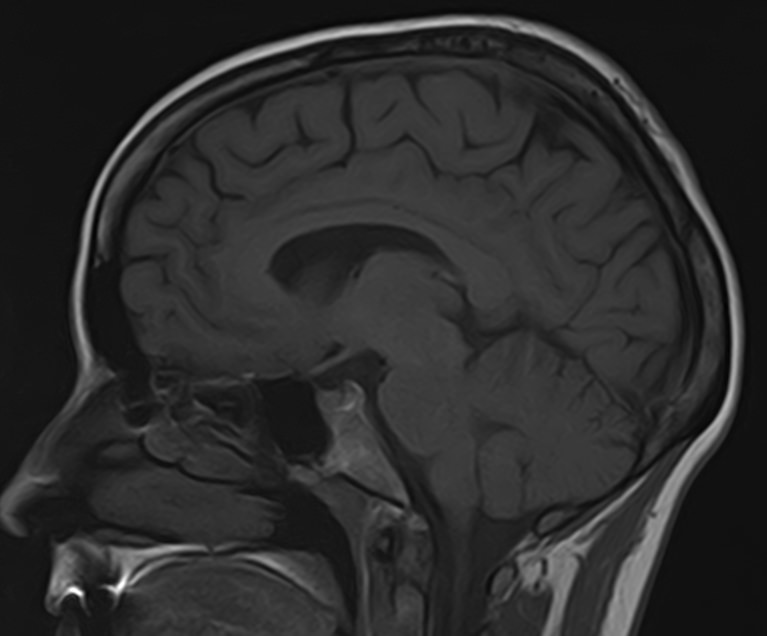

Золотым стандартом современной диагностики патологии головного мозга является магнитно-резонансная томография. Высокая информативность, отсутствие вредного рентгеновского излучения, быстрота и доступная цена исследования являются основными преимуществами данной методики.

В клинике “Доступная медицина” возможно одновременно выполнить МРТ головного мозга и МР-ангиографию сосудов головного мозга. Исследование проводится на современном томографе TOSHIBA VANTAGE TITAN 1,5 Тесла, который является аппаратом с высокой разрешающей способностью и используется для точной диагностики заболеваний центральной нервной системы.

Стандартная МРТ головного мозга дает важную информацию о состоянии и структуре мозговой ткани для выявления большого числа заболеваний, в том числе опухолевых образований, демиелинизирующих заболеваний, воспалительных процессов головного мозга и мозговых оболочек. Стандартную МРТ головного мозга дополняет МР-ангиография, которая отображает состояние системы кровоснабжения головы и шеи. Компьютерная программа обрабатывает данные, полученные при сканировании, и формирует объемные изображения как самого мозга, так и сосудистой системы в отдельности без прилегающих тканей. Обе методики применяются одновременно и взаимодополняют друг друга, давая полную диагностическую картину.

Исследование предоставляет информацию о состоянии тканей головного мозга и оболочек, проходимости кровеносных сосудов, наличии и размерах опухолей, тромбов, гематом и других патологий. Изучив изображения, нейрохирург или другой специалист получает информацию о локализации патологии, степени повреждения тканей мозга, может принять решение о проведении операции либо контролировать ход лечения.